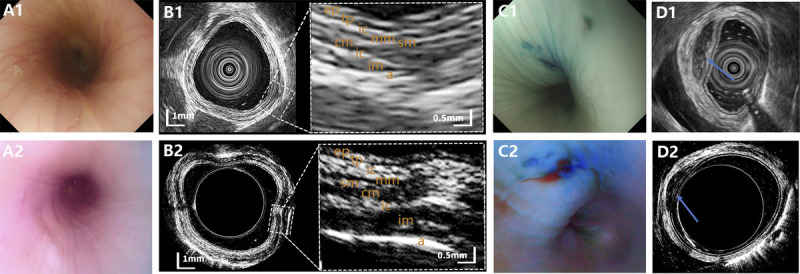

Results: Under the optical mode of USCE, the GI tract was well visualized, and all simulated lesions were located. Clear ultrasound images of normal GI tract and submucosal lesions were acquired. Ultrasound images of the esophagus, stomach, and small bowel were characterized by differentiated multilayer structures on USCE, which was consistent with the structures displayed on EUS. And the visualization of submucosal lesions, using both USCE and EUS, was characterized by a hypoechoic and well-demarcated mass in the layer of submucosa.

Abstract Image